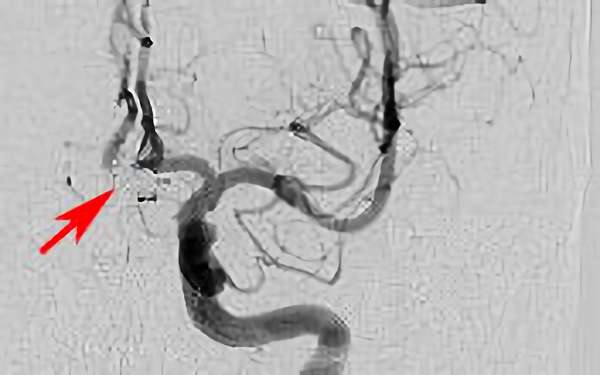

左椎骨動脈後下小脳動脈分岐部動脈瘤

70代

院内外来

No.1628 手術前

No.1628 手術中

No.1628 手術後